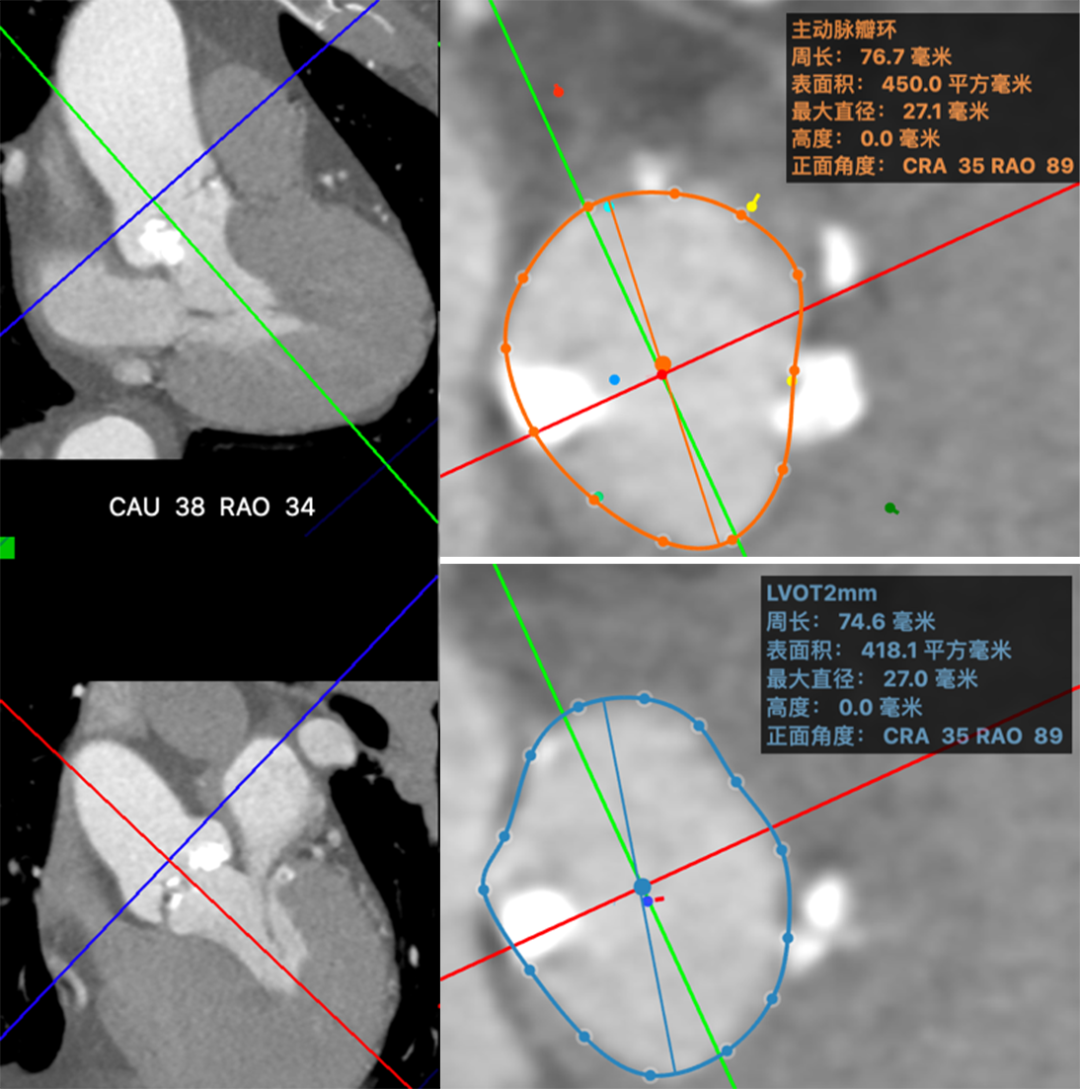

术前CT评估 >>>>>>

主动脉瓣评估:患者为三叶式主动脉瓣,瓣叶可见多发斑点团片结节状钙化,瓣环见粗大钙化,瓣环周长77 mm,瓣口开放面积61 mm2,左室流出道见条片状钙化。

经过复旦中山葛均波院士、周达新教授团队的仔细探讨,该患者主动脉瓣瓣叶、左室流出道钙化严重,球囊预扩、瓣膜释放过程中都存在脑卒中风险,因此该患者适合置入脑?;ぷ爸孟陆?/font>TAVR。结合该患者的超声及CT分析,最终考虑选择20 mm微创球囊充分扩张后,植入24 mm VitaFlow瓣膜。